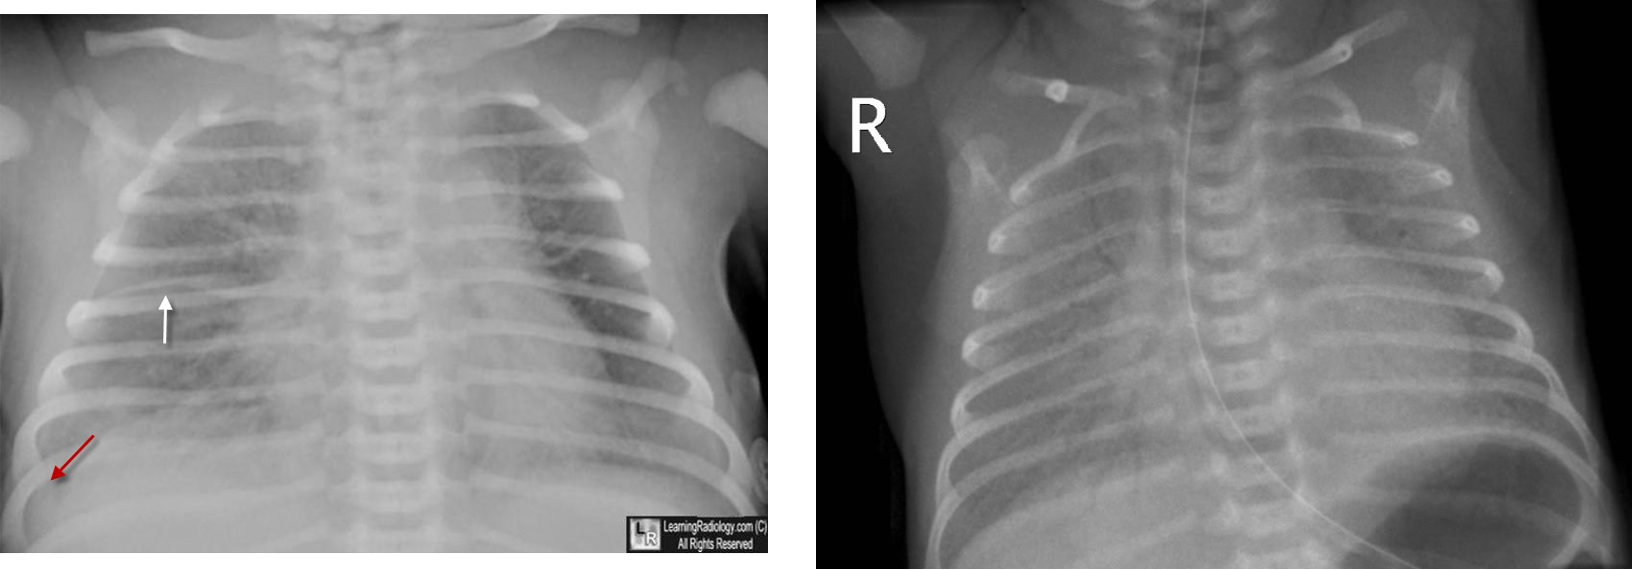

- A chest radiograph: cardiomegaly, narrow mediastinum, and increased pulmonary vasculature. ECG: RAD and RVH

Imaging

- Small to N cardiac silhouette

- Decrease pulmonary vasculature